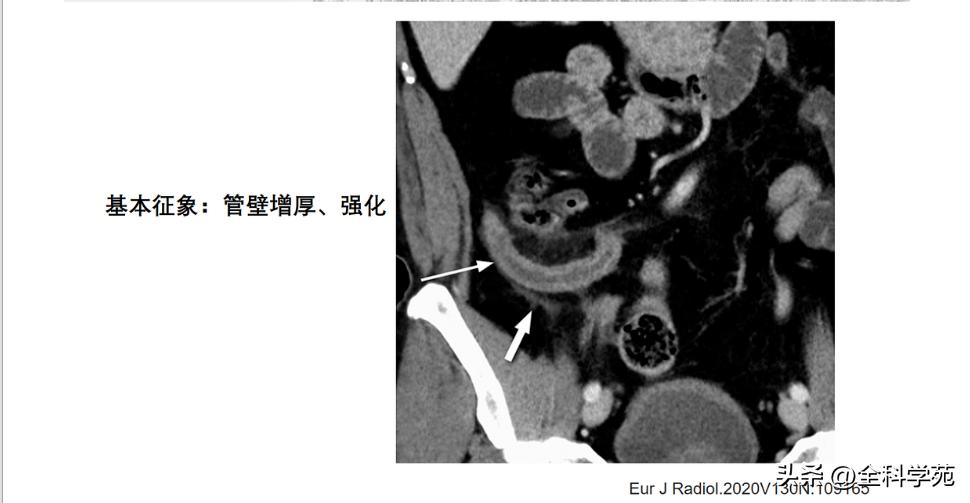

◆ 阑尾壁增厚

>3mm

CT: 阑尾壁明显增强

6-10 mm 伴阑尾壁增厚、壁明显强化,周围脂肪间隙模糊或分层(靶征或牛眼征,表明粘膜下水肿的液体含量vs 气体含量